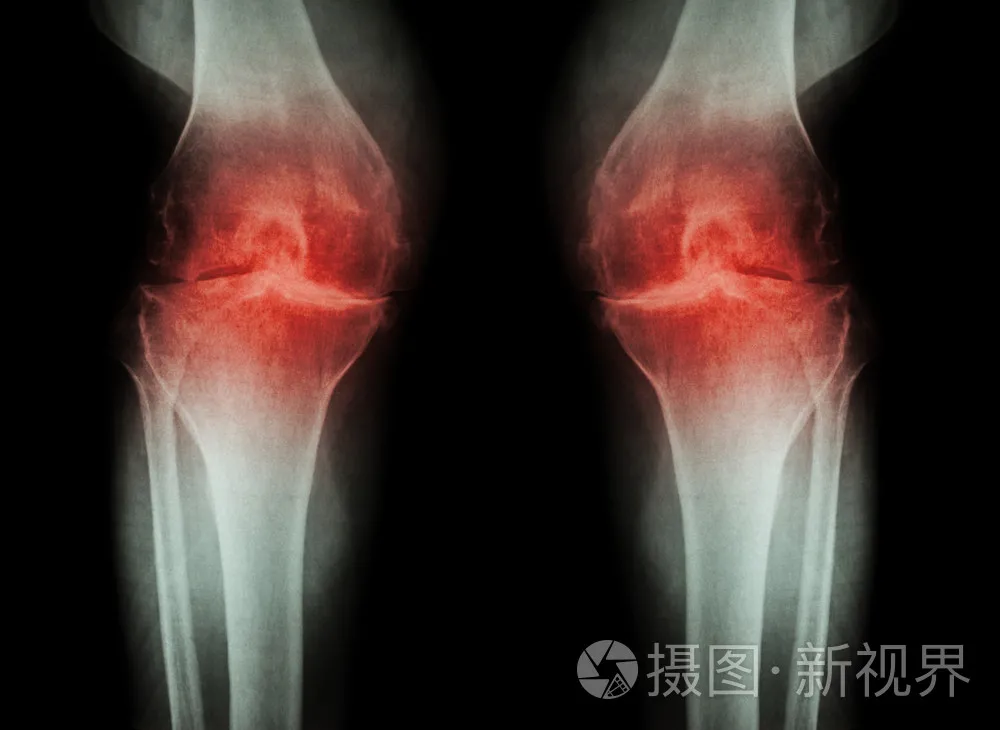

骨關節炎的起因是關節軟骨的磨損,因此隨著年齡越大,關節的退變越易發生,也越容易患病。

圖源:攝圖網

據調查發現,65歲以上老年人中骨性關節炎發病率為60%-70%,而75歲以上人群高達85%左右。

而膝關節作為人體最大的負重關節,是骨關節炎的最常患病部位,也就是說約半數以上老人忍受著膝蓋疼痛的困擾。